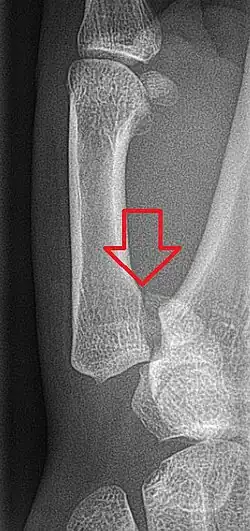

Bennett's fracture or Bennett fracture is a type of partial broken finger involving the base of the thumb, and extends into the carpometacarpal (CMC) joint.[1]

This intra-articular fracture is the most common type of fracture of the thumb, and is nearly always accompanied by some degree of subluxation or frank dislocation of the carpometacarpal joint.

Though these fractures commonly appear quite subtle or even inconsequential on radiographs, they can result in severe long-term dysfunction of the hand if left untreated. In his original description of this type of fracture in 1882, Bennett stressed the need for early diagnosis and treatment in order to prevent loss of function of the thumb CMC joint, which is critical to the overall function of the hand.[4]